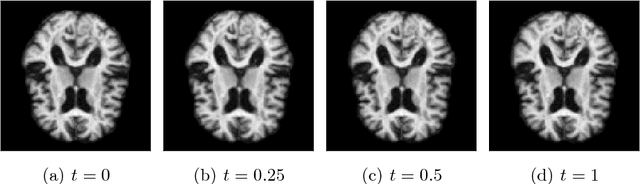

Abstract:Interpolation in generative models allows for controlled generation, model inspection, and more. Unfortunately, most generative models lack a principal notion of interpolants without restrictive assumptions on either the model or data dimension. In this paper, we develop a general interpolation scheme that targets likely transition paths compatible with different metrics and probability distributions. We consider interpolants analogous to a geodesic constrained to a suitable data distribution and derive a novel algorithm for computing these curves, which requires no additional training. Theoretically, we show that our method locally can be considered as a geodesic under a suitable Riemannian metric. We quantitatively show that our interpolation scheme traverses higher density regions than baselines across a range of models and datasets.